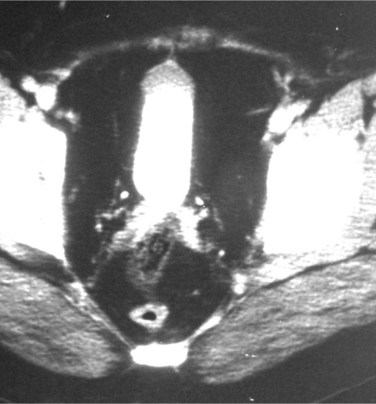

MRI offers cross-sectional and multiplanar evaluation of the retroperitoneal fibrosis plaque (Fig. 40–12). Theoretically, MRI allows superior soft tissue discrimination and can more accurately distinguish the plaque from the great vessels than unenhanced CT. In addition, the disease can be followed without the radiation exposure of repeated CT (Burn et al, 2002). Fat saturation images are recommended to permit optimal discrimination from surrounding tissues (Elsayes et al, 2007; Cronin et al, 2008). Typically, T1-weighted images of the lesion reveal low to medium signal intensity (hypointense compared with muscle); T2-weighted imaging is variable. Low T2 signal intensity has been correlated with mature plaque (Mulligan et al, 1989). High signal intensity on T2-weighted images suggests increased water content and hypercellularity and may be due to inflammation associated with retroperitoneal fibrosis. However, the latter may be due to an underlying malignant process (Amis, 1991; Burn et al, 2002). A low intensity signal is present if the majority of the plaque is composed of fibrosis. With gadolinium administration, variable enhancement of the plaque may be seen, with a greater degree of enhancement in the more acute phases of the disease process. Enhancement ratios can be calculated with dynamic gadolinium enhancement, and investigators have used these ratios to assess disease activity and monitor treatment responses (Burn et al, 2002). 18F-fluorodeoxyglucose positron emission tomography (F-18 FDG PET) is an imaging modality that detects hypermetabolic activity. It may depict the degree of inflammation in the plaque, which may predict response to immunosuppressive therapy as well as its therapeutic response (Vaglio et al, 2006; Young et al, 2008). The utility of F-18 FDG PET for management of retroperitoneal fibrosis is not yet defined; thus, further studies are warranted. Gallium-67 single photon emission–computed tomography (SPECT) scintigraphy has been used for evaluating responses to medical therapy of retroperitoneal fibrosis and for detection of recurrent disease. It demonstrates both the mass lesion and its inflammatory component (van Bommel et al, 2007).

Figure 40–12 Unenhanced magnetic resonance imaging from the same patient as in Figure 40–9.

(Courtesy of Dr. Ronald Zagoria.)